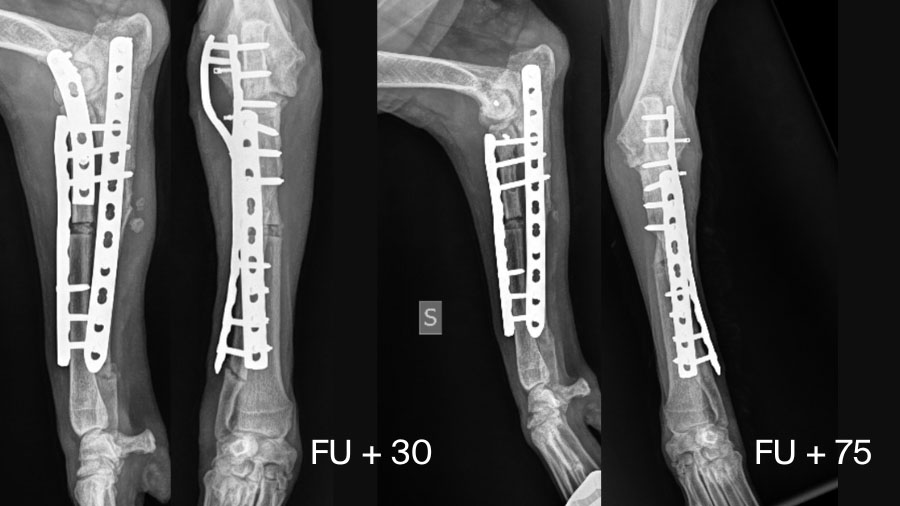

Postoperative management is just as critical as the surgery itself. Recovery is typically gradual. In this case, the dog showed steady improvement in limb loading and muscle mass over several weeks. Serial radiographs every two weeks monitored the healing of both the ulnar fracture and the radial ostectomy site. At 30 days, radiographic evidence supported removal of the trans-articular plate, which was performed around six weeks postoperatively.

Functionally, the patient regained good limb use, satisfactory elbow range of motion, and restoration of muscle mass. While physiotherapy is strongly recommended to enhance recovery, owner compliance may vary. Nevertheless, with vigilant monitoring and timely intervention, chronic Monteggia fractures can achieve positive outcomes.